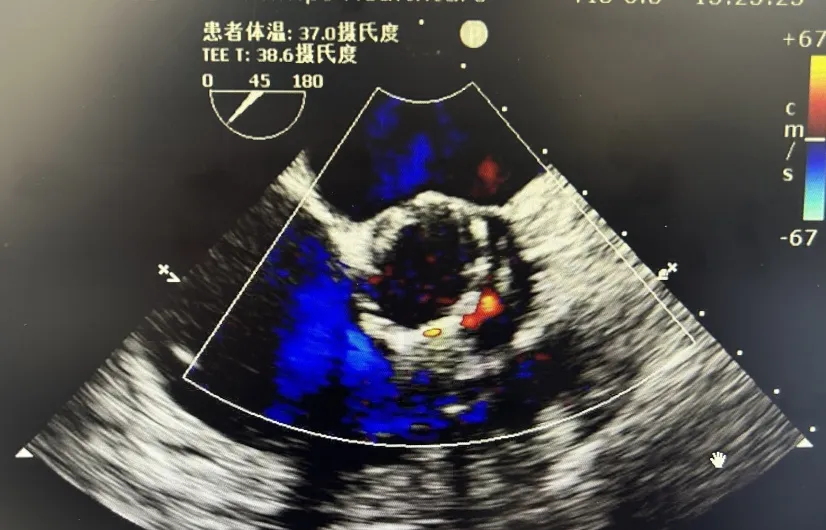

李有金教授 宁夏回族自治区人民医院 “随着人口老龄化加剧,主动脉瓣狭窄患者数量逐年增多,其中高龄、合并多种基础疾病的复杂病例占比不断提升。经导管主动脉瓣置换术(TAVR)作为微创治疗技术,已成为此类患者的重要治疗选择。对于高龄、有恶性肿瘤病史的患者而言,手术的安全性、微创性与长期疗效同等重要,既要最大程度降低手术创伤与并发症风险,也要确保瓣膜的耐用性与患者术后生活质量。 全球首款预装干瓣ProStyle A®的临床应用,为复杂病例治疗提供了全新解决方案。该瓣膜无需术中戊二醛冲洗,大幅缩短了手术操作时间,尤其适合高龄、心功能欠佳的患者。其独特的抗钙化工艺与优化的瓣架设计,既保证了瓣膜的长期耐久性,又能有效规避冠脉风险,为患者的“全生命周期管理”奠定了坚实基础。” 病例简介 现病史:患者半月余前突发抬头时一过性头晕,持续数秒钟,每日发作3-5 次,伴天旋地转感,症状可自行缓解。2025年12月12日就诊于外医院,心脏彩超提示“主动脉瓣狭窄(重度)并关闭不全(轻度),左室壁增厚,升主动脉增宽,左心室收缩功能正常,舒张功能减退”,建议转上级医院诊治。为求进一步治疗,患者就诊我院,门诊以“主动脉瓣狭窄”收住入院。 既往史:胃癌,胃大部切除术后五年。 临床诊断:“1.主动脉瓣狭窄伴有关闭不全(重度狭窄伴轻度关闭不全);2.主动脉瓣钙化;3.肥厚性非梗阻性心肌病;4.心功能不全;心功能III级(NYHA分级);5.升主动脉扩张;6.胃恶性肿瘤个人史” 术前CT评估显示:Type-1型二叶瓣,R-N钙化粘连,瓣叶重度钙化,主要分布在无冠窦瓣叶游离缘、R-N对合缘粘连处及右冠窦基底部;钙化积分933.2mm³;主动脉瓣环直径26mm,LVOT 27.6mm;双侧瓣叶开口高度可,左冠开口高度22.0mm,右冠开口高度20.0mm;主动脉水平夹角57.7°,左室内径偏小;主动脉弓部75.1°锐角弓;外周入路无明显迂曲及钙化,双侧股动脉内径可,右股中分叉。 手术策略 右侧股动脉为主入路,左侧为辅助入路,20F大鞘,股骨头中段穿刺;预装金仕生物 ProStyle A® AV26瓣膜,备29瓣膜,22mm球囊预扩;初始定位对齐瓣环上5mm超高位释放,释放过程中使瓣膜自然下滑至工作位,最终理想位置零位,利用瓣上锚定与封堵,规避冠脉风险;术前适当补液; 手术过程 Step1:主动脉根部造影; 主动脉根部造影 Step2:使用“先瑞达”22mm球囊预扩,无腰无漏,冠脉充盈良好; 球囊预扩 Step3:将ProStyle A®预装干瓣送至目标位置,初始定位后缓慢释放,观察瓣膜自然下滑至理想工作位; 定位 释放至工作位观察 Step5:瓣膜完全释放后,再次造影,显示瓣膜位置、形态良好,导管测平均跨瓣压差由术前60mmHg-降至1mmHg,冠脉血供正常; 最终造影 Step6:术后即刻超声监测,人工瓣膜位置固定,瓣叶启闭无受限,瓣周少量反流。 术后患者病情稳定,已于一周后出院。 结语 作为宁夏回族自治区心血管疾病诊疗的核心高地与区域医疗中心建设的标杆单位,宁夏回族自治区人民医院始终坚守“敬佑生命、救死扶伤”的医者初心,以“技术引领、学科兴院”为发展理念,在心脏大血管领域持续深耕,构建了集“精准评估-个性化方案-微创治疗-全程康复”于一体的诊疗体系。此次西北首例ProStyle A®预装干瓣植入手术的圆满成功,不仅是医院在复杂结构性心脏病介入治疗领域的又一突破性成果,更彰显了医院在引进前沿技术、转化创新器械、服务复杂重症患者方面的责任与担当。 Prostyle A®预装干瓣——助力临床最优化解决方案: 预装干瓣 便捷顺安:金仕生物专利抗钙化技术运用纳米技术去除组织内的细胞碎片和磷脂,封闭游离醛基,从根本上阻断了瓣膜钙化的多项因素,显著提升了瓣膜的耐久性;同时,相比较传统戊二醛保存方式,干式存储最大限度的保留心包的亲水亲油平衡,还原组织天然曲柔性,进一步保障了瓣叶开合,保证长期耐久性; 平衡径向支撑力:Prostyle A®瓣架网孔比例按照病例解剖结构的特殊设计,使瓣膜在狭窄最重的地方良好的撑开,同时避免对瓣环及周边组织的过度压迫,有效降低传导阻滞风险; 精准释放:底部桶状设计更易迅速锚定,协同释放张力小,助力最终精准释放; 过弓柔顺:较细的输送系统直径+亲水涂层,显著提升输送系统通过性,有效减少血管并发症的发生,内连鞘版本最小尺寸等效14F大鞘; 专家简介 李有金 宁夏回族自治区人民医院(点击查看专家详细简历) · END ·